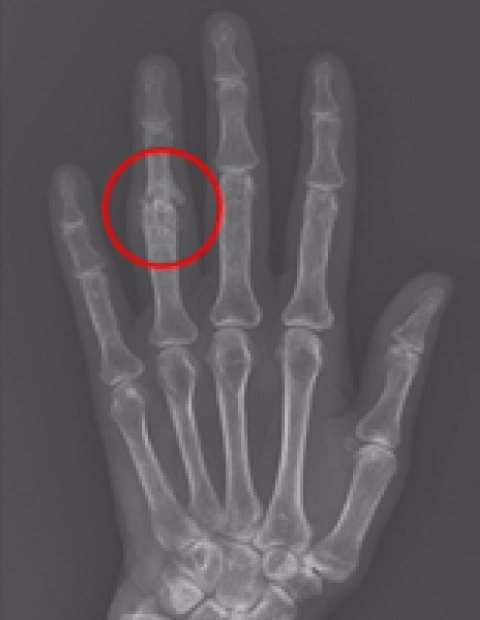

손가락 인공관절 수술

2016.04.01

2016.09.09